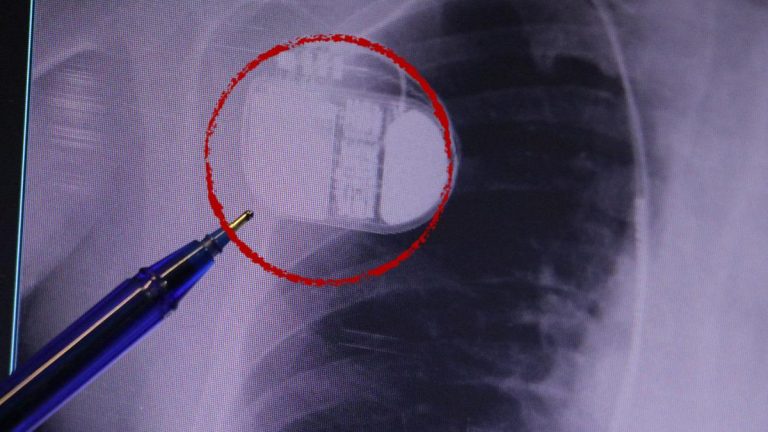

Kolon Kanseri Ailede Varsa, Taramalara 10 Yaş Önce Başlayın!